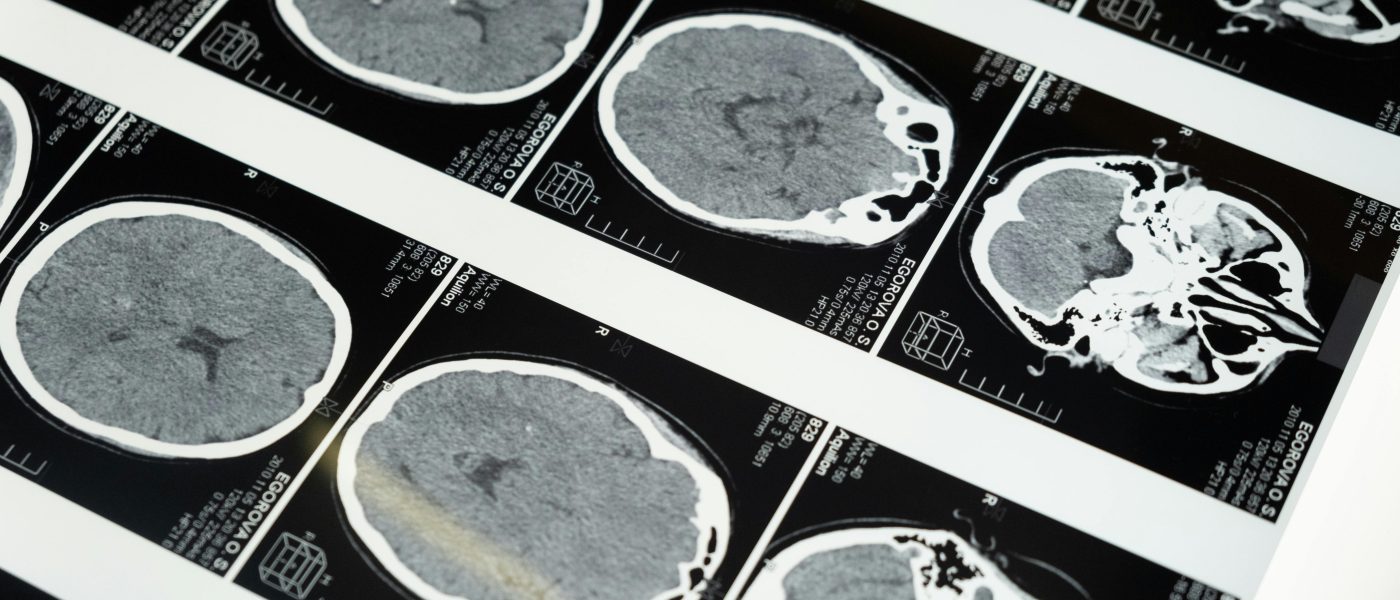

Proteína CgA: A Chave Oculta na Resiliência Cerebral contra Alzheimer

Novo estudo revela que a proteína Chromogranin A (CgA) pode ser um fator chave na proteção natural do cérebro contra o Alzheimer, mesmo na presença de marcadores da doença. Entenda as implicações.